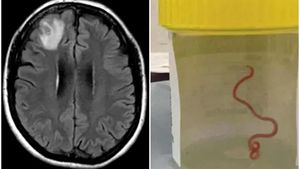

Primul caz de acest gen din istorie. Medicii au rămas șocați când au găsit acest organism viu în creierul unei femei

Caz șocant în Australia! Medicii au descoperit un vierme viu care se zbătea în creierul unei femei. Este pentru prima dată când au avut de-a face cu așa ceva. Femeia, în vârstă de 54 de ani, se confrunta cu diverse probleme de sănătate din cauza „musafirului” nepoftit, printre care pierderi de memorie și depresie. În […]